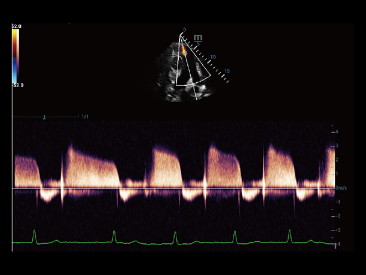

Since the company was founded, Mindray has been continuously exploring new ways to improve diagnostic confidence. Powered by the most revolutionary ZONE Sonography? Technology, Resona 7ŌĆÖs new ZST+ platform brings ultrasound image quality to a higher level by zone acquisition and channel data processing.

As well as the premium level image quality, Resona 7 also enhances clinical research capabilities with the revolutionary V Flow for vascular hemodynamic evaluation, and the most intelligent plane acquisition from 3D datasets for fetal CNS diagnosis. Combining the most intuitive gesture-based multi-touch operation and all the essential clinical features, Resona 7 is truly leading new waves in ultrasound innovation.